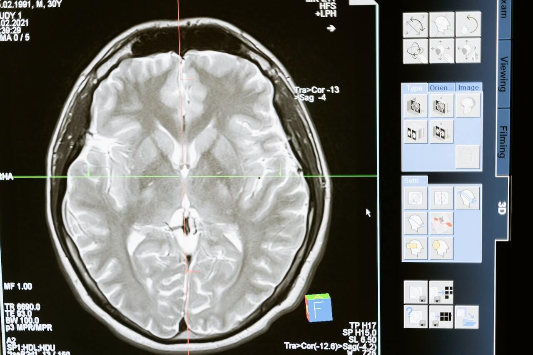

뇌는 우리의 인지 기능을 담당합니다. 인지 기능은 우리의 삶의 질과 밀접한 관련이 있습니다. 건강한 인지 기능은 우리가 문제를 해결하고, 정보를 습득하고, 사회적 관계를 유지하고, 목표를 달성하는 데 도움이 됩니다. 이 글에서는 건강한 뇌와 인지 기능을 위한 4가지 팁을 소개합니다. 이 팁들은 과학적 연구에 근거하여 제시된 것이며, 실제로 효과가 입증된 것들입니다. 이 팁들을 따르면 뇌의 혈류와 산소 공급을 증가시키고, 뇌 세포의 성장과 연결을 촉진시키고, 뇌의 플라스틱성과 유연성을 개선시키고, 인지 기능의 저하를 예방하거나 완화시킬 수 있습니다.